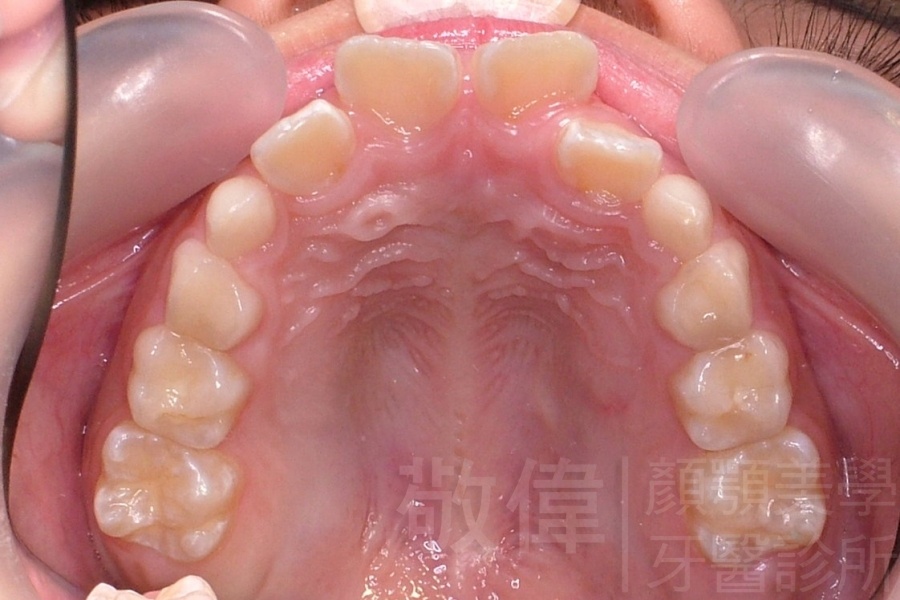

齒顏矯正/上顎暴牙且牙齒極度混亂

矯正前-上   矯正前-下

<個案說明>

上顎暴牙且牙齒極度混亂,經由矯正之後,臉型大幅度改善,牙齒的排列更加的整齊健康。相較於之前眼神充滿精神,自信心展現無遺。